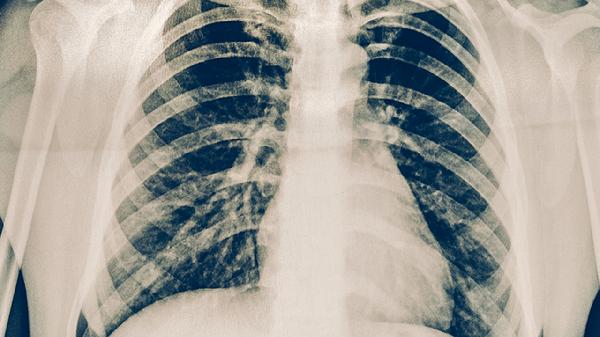

肺结核早期最常见的症状是咳嗽,通常持续2周以上。咳嗽初期可能为干咳,随着病情发展可能出现咳痰,痰液可能呈现白色黏液状或带有血丝。咳嗽在早晨或夜间可能加重,影响正常休息。肺结核引起的咳嗽与普通呼吸道感染不同,常规止咳药物效果有限。若咳嗽持续不缓解,建议及时就医进行胸部影像学检查和痰液结核菌检测。

肺结核早期症状缺乏特异性,容易与其他呼吸道疾病混淆。若出现上述症状持续2周以上,建议及时到呼吸内科或感染科就诊。确诊肺结核后应严格遵医嘱进行规范抗结核治疗,常用药物包括异烟肼片、利福平胶囊、吡嗪酰胺片、乙胺丁醇片和链霉素注射液等。治疗期间应注意休息,保持室内通风,避免传染他人。饮食上应保证充足热量和优质蛋白摄入,适当补充维生素和矿物质。定期复查胸部影像学和肝功能,监测治疗效果和药物不良反应。完成全程治疗是治愈结核病的关键,不可擅自停药或减量。